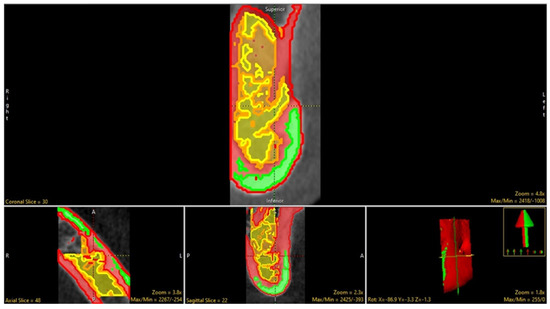

2.3. Segmentation (Manual and Semi-Automatic)

2.4. Measurement and Tabulations via BMA